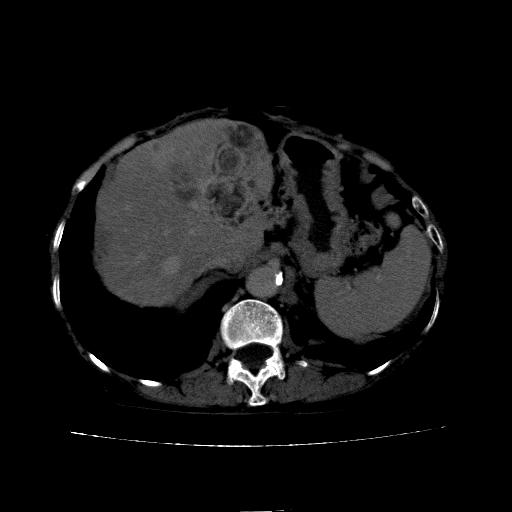

延迟期

看片子胆管里结石,肝上显示的占位会不会是胆管癌?大家帮忙看看,图像不太好,手头的处理文件没有,大致转换了一下,有原始图像数据

胆管细胞癌,胃壁增厚

支持胆管细胞癌诊断,胃壁增厚。

1)考虑肝左叶胆管细胞癌并肝内转移。2)肝左叶肝内胆管结石。